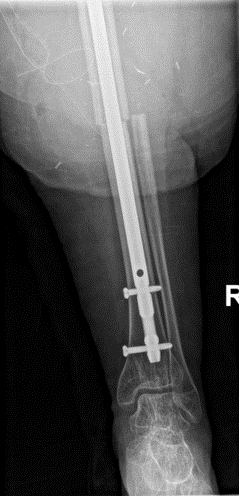

Case presentation: 70 yo F presents to clinic s/p short CMN of left intertroch fx at outside facility in Aug 2022 with worsening left hip pain, inability to bear weight. No pertinent PMHx. Workup and treatment plan?

Infxn workup negative, Lateral approach used, Wagner osteotomy to facilitate nail removal, autograft from femoral/neck 50 cc allograft to graft defect in posterior column, multihole cup/screws w/ dual mobility, modular fluted tapered stem.

ETO was performed 15cm in length, Cables were deeply imbedded in bone and had to be cut through with ETO, trephine over the remaining distal stem. Revised to modular fluted tapered stem.